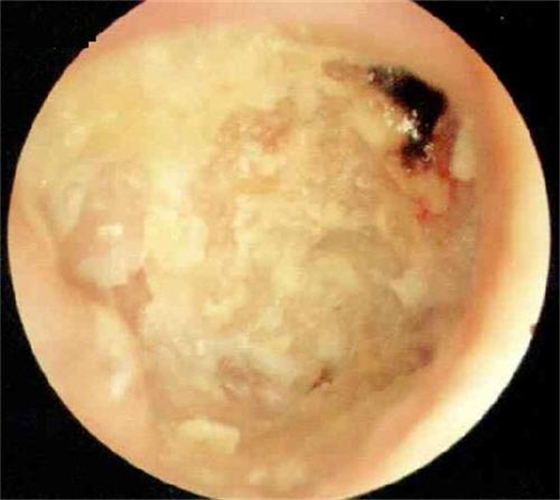

中耳炎使鼓膜穿孔